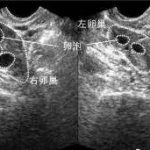

尿促卵泡素是从绝经期妇女尿中提取纯化而来,其活性成分是 FSh,FSh 具有促进卵泡募集与发育的作用。对于非原发性卵巢功能衰竭的妇女,尿促卵泡素能刺激卵巢卵泡发育。在缺少内源性 Lh 峰的情况下,当监测结果显示卵泡已充分发育时,注射本品后应注射人绒毛膜促性腺激素(hCG),以促进卵泡充分发育成熟和排卵。